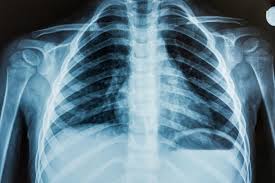

Full Body Scans

A full body scan provides a comprehensive, non-invasive assessment of your vital organs and tissues, helping detect potential health concerns early—often before symptoms appear—so you can take proactive control of your long-term wellbeing.

Standard Full Body Scan

(Bangkok)

Standard full body scan recommended for those ages between 30 - 50 years old.

EKG + X Ray